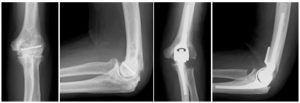

人工肘関節2

肘関節骨折に対し他院で手術を受けられましたが、肘の痛みと運動制限が残存し人工肘関節置換術を施行しました。痛みは消失し、可動域もほぼ正常に回復されました。